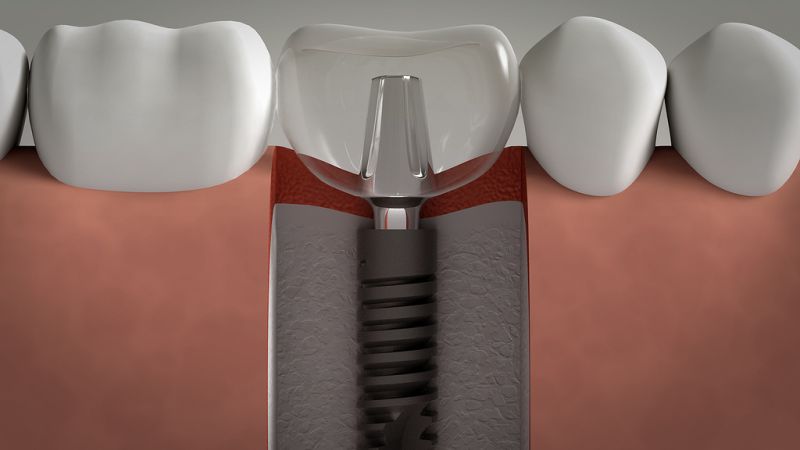

ایمپلنت به گونه ای است که از آن می توان برای تمامی دندان ها و یا یک یا چند دندان استفاده کرد. و به کمک این روش به ترمیم دندان ها پرداخت. با این وجود افرادی که دندان شماره 7 آنها با مشکل مواجه شده است. و نیاز به ترمیم دارد، می توانند از روش ایمپلنت دندان 7 برای ترمیم این دندان استفاده کنند که در این صورت همه دندان های آنها ترمیم نمی شود بلکه فقط دندان شماره 7 ترمیم می گردد.

برای اینکه ایمپلنت برای دندان شماره 7 انجام شود، ابتدا شخص مورد نظر باید به پزشک مراجعه کند تا شرایط او تحت بررسی قرار بگیرد. سپس با معاینه پزشک در صورتی که این شخص مشکلی در استخوان فک نباشد و یا عفونت دندان نداشته باشد، برای درمان او اقدام می گردد که در این مرحله فضای دندان شماره 7 برای جایگذاری ایمپلنت آماده سازی می شود تا پزشک بتواند پایه ایمپلنت را در داخل استخوان فک دندان شماره 7 جایگذاری کند.

این عملیات تحت بی حسی موضعی انجام می شوند تا بیمار درد زیادی را احساس نکند. سپس بعد از اینکه پایه ایمپلنت برای فرد جایگذاری شد، باید مدت زمانی از نصب آن در دهان بگذرد تا پزشک بتواند روکش ایمپلنت را نصب کند. در انتها روکش ایمپلنت بر روی دندان قرار داده می شود و مراحل ایمپلنت دندان 7 با نصب روکش پایان می یابد.